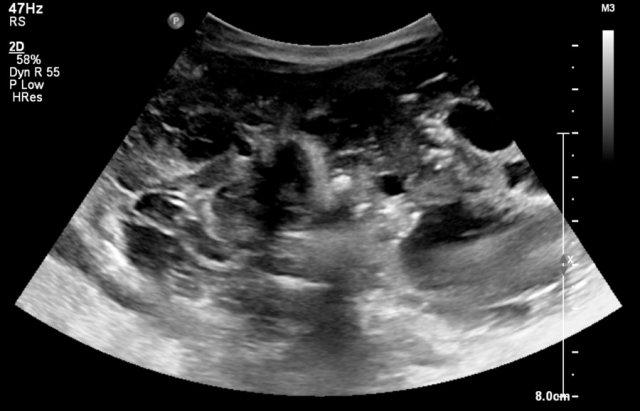

Bé trai 4 tháng tuổi với một khối lớn trong ổ bụng. Siêu âm cho thấy hỗn hợp thành phần đặc và dạng nang. Khối u tách biệt với các tạng đặc trong ổ bụng.

MRI cho thấy khối u có thành phần vừa dạng nang vừa đặc. Trong phẫu thuật, một u quái lành tính của thành dạ dày đã được cắt bỏ.